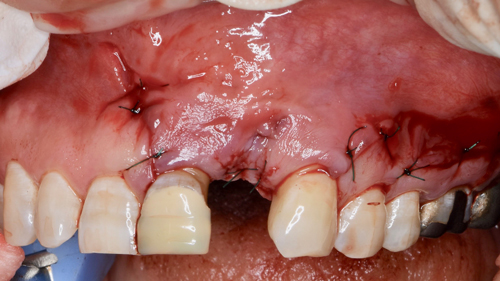

患者様は、迷わずインプラントを選択されました。抜歯と同時にインプラントの移植と自己血液を用いた骨の造成再生術を行われました。

腫瘍が骨を大きく溶かしていましたので、欠落した部分にCGFに人工の骨を混ぜ合わせ、骨の再生をインプラントの移植と同時に試みました。

手術直後の状態です。

患者様は静脈麻酔鎮静法(無料)を受けながらの施術でしたので、手術中の記憶は殆ど無かったとのこと。